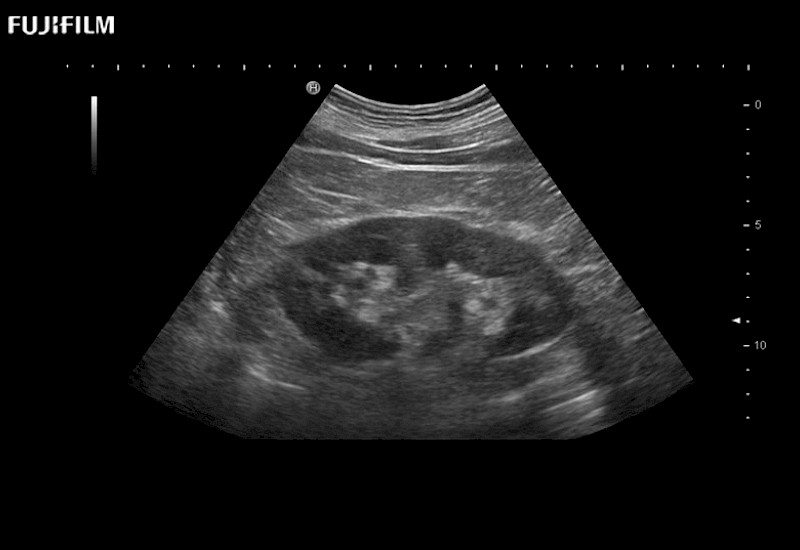

Exclusive linear array robotic surgery transducer.

Features: